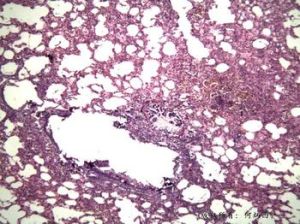

α 1 -抗胰蛋白酶是肝臟產生的一種糖蛋白,是人體內血清蛋白溶解酶(如胰蛋白酶)的主要抑制物.唾液,十二指腸液,呼吸道分泌物,淚液,鼻腔分泌物和腦脊液中都含有α1 -抗胰蛋白酶.α1 -抗胰蛋白酶基因位於第14號染色體,70位等位基因調控其合成.血清α1 -抗胰蛋白酶的水平降低,由於蛋白酶的活性,尤其是彈性蛋白酶的活性未被抑制,導致肝細胞的破壞.

α1-AT具有較強的血管通透性,在肺組織中的濃度較其它絲氨酸蛋白酶抑制因子或α2-巨球蛋白的濃度高,而且對NE的專一性更強,因而它主要抑制肺臟中彈性蛋白酶的活性,保護肺部不受彈性蛋白酶的酶解損傷。α1-AT抑制蛋白酶的過程是一個自毀模式的反應過程,α1-AT除了被其捕獲的蛋白酶緩慢裂解外,同時α1-AT-蛋白酶複合物能被吞噬細胞識別、吞噬、從血漿中清除。在酶抑制過程中,α1-AT與蛋白酶活性中心的結合模式與蛋白酶-底物的結合模式相似。α1-AT捕獲目標酶,並與目標酶結合形成α1-AT-蛋白酶1:1的共價複合物,蛋白酶對結合的α1-AT產生緩慢的酶解,α1-AT構象由S型向R型轉換,封閉了蛋白酶的反應中心從而達到抑制蛋白酶活性的作用。